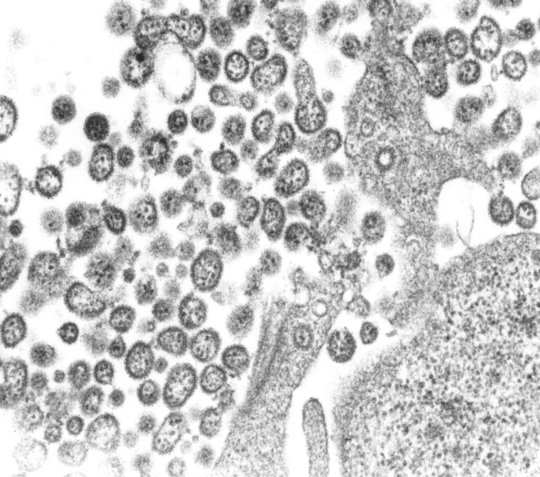

Virale RNA löst kritische Schritte im Lebenszyklus des Lassavirus aus

Das Lassavirus (LASV) gehört zur Familie der Arenaviren und ist ein RNA-Virus, das heißt, es speichert seine Erbinformation im Gegensatz zu DNA-Viren in Form von RNA. Das Lassavirus kommt in westafrikanischen Ländern vor und kann das hämorrhagische Lassafieber auslösen. Jährlich infizieren sich zwischen 100.000 und 300.000 Menschen mit dem LASV, von denen ca. 5.000 Personen sterben. Um die Krankheit auszulösen, muss sich das Virus effizient in den Zellen der infizierten Person vermehren. Wesentliche Schritte im Lebenszyklus des Lassavirus sind der Eintritt in die menschliche Wirtszelle, die Vervielfältigung der Viren-RNA, das Verpacken der neuen Viren-RNA mit viruseigenen Proteinen und der Austritt aus der Wirtszelle.